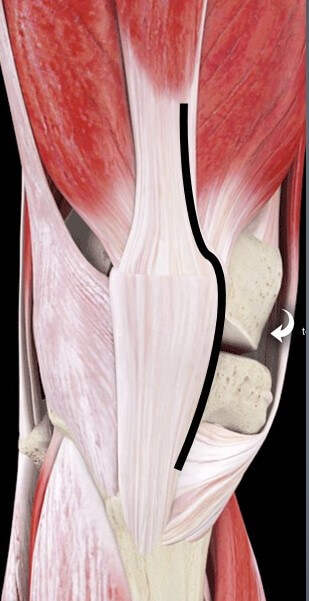

人工膝関節置換術の手術をする際には

通常内側広筋を切開する方法(Medial parapatellar approach)が一般的です。

黒い線が切開線

(3D4medicalを引用)

しかし、

私はなるべく筋肉をダメージを与えずに

手術を行うことが大事だと思っていますので

人工股関節置換術の手術と同様に

筋肉を切らないアプローチを用いて人工膝関節置換術を行っています。

内側広筋を切らないアプローチ(Subvastus approach)です。